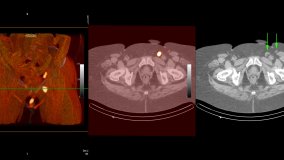

It is divided into two major types: those that have an excellent resolution and provide precise anatomical details e.g., computed tomography (CT) and magnetic resonance (MR) and those that generate a representation of the function of organs or tissues being analysed also known as Molecular Imaging such as Single Photon Emission Computed Tomography (SPECT) and Positron Emission Tomography (PET).

Imaging technologies are fast-growing and evolving disciplines that allow the visualization, characterisation and quantification of anatomical lesions or biologic events that occur at early stages of disease. The past two decades have seen the development of hybrid imaging, which combines the anatomical and functional images such as SPECT/CT, PET/CT and PET/ MR . Thus, generating a powerful tool for the diagnosis of several health conditions, in particular non-communicable diseases such as cardiovascular diseases, cancer, neurodegenerative disorders and diabetes which are the leading causes of mortality worldwide and that represent a burden on health care systems.